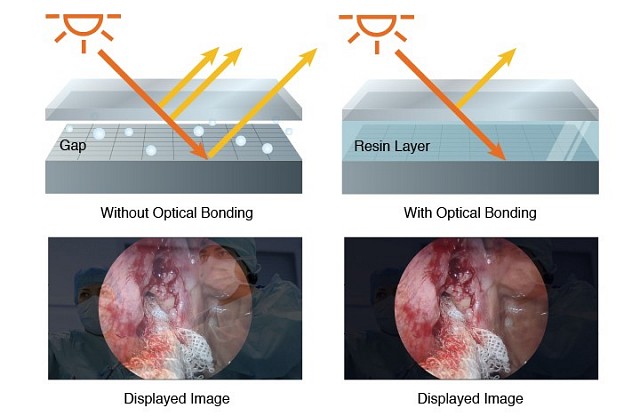

- 光学粘合可减少反射,高耐久性,防冷凝

所使用的保护玻璃硬度超过 9H,不易划伤。光学粘合通过在液晶面板和外部玻璃之间的气孔中注入光弹性树脂,进一步提高了物理强度。由于液晶面板和外部玻璃之间没有缝隙,因此可以防止灰尘和湿气对液晶面板造成损坏。

在温度剧烈波动的环境中使用显示器时,液晶面板和保护玻璃之间的气孔中可能会出现冷凝水。使用光学胶合技术后,就不会出现气孔,这意味着不会产生冷凝水,也不会影响可视性。使用的保护玻璃硬度超过 9H,不易划伤。光学胶合技术通过在液晶面板和外部玻璃之间的气孔中注入光弹性树脂,进一步提高了物理强度。由于液晶面板和外部玻璃之间没有缝隙,因此可以防止灰尘和湿气对液晶面板造成损坏。